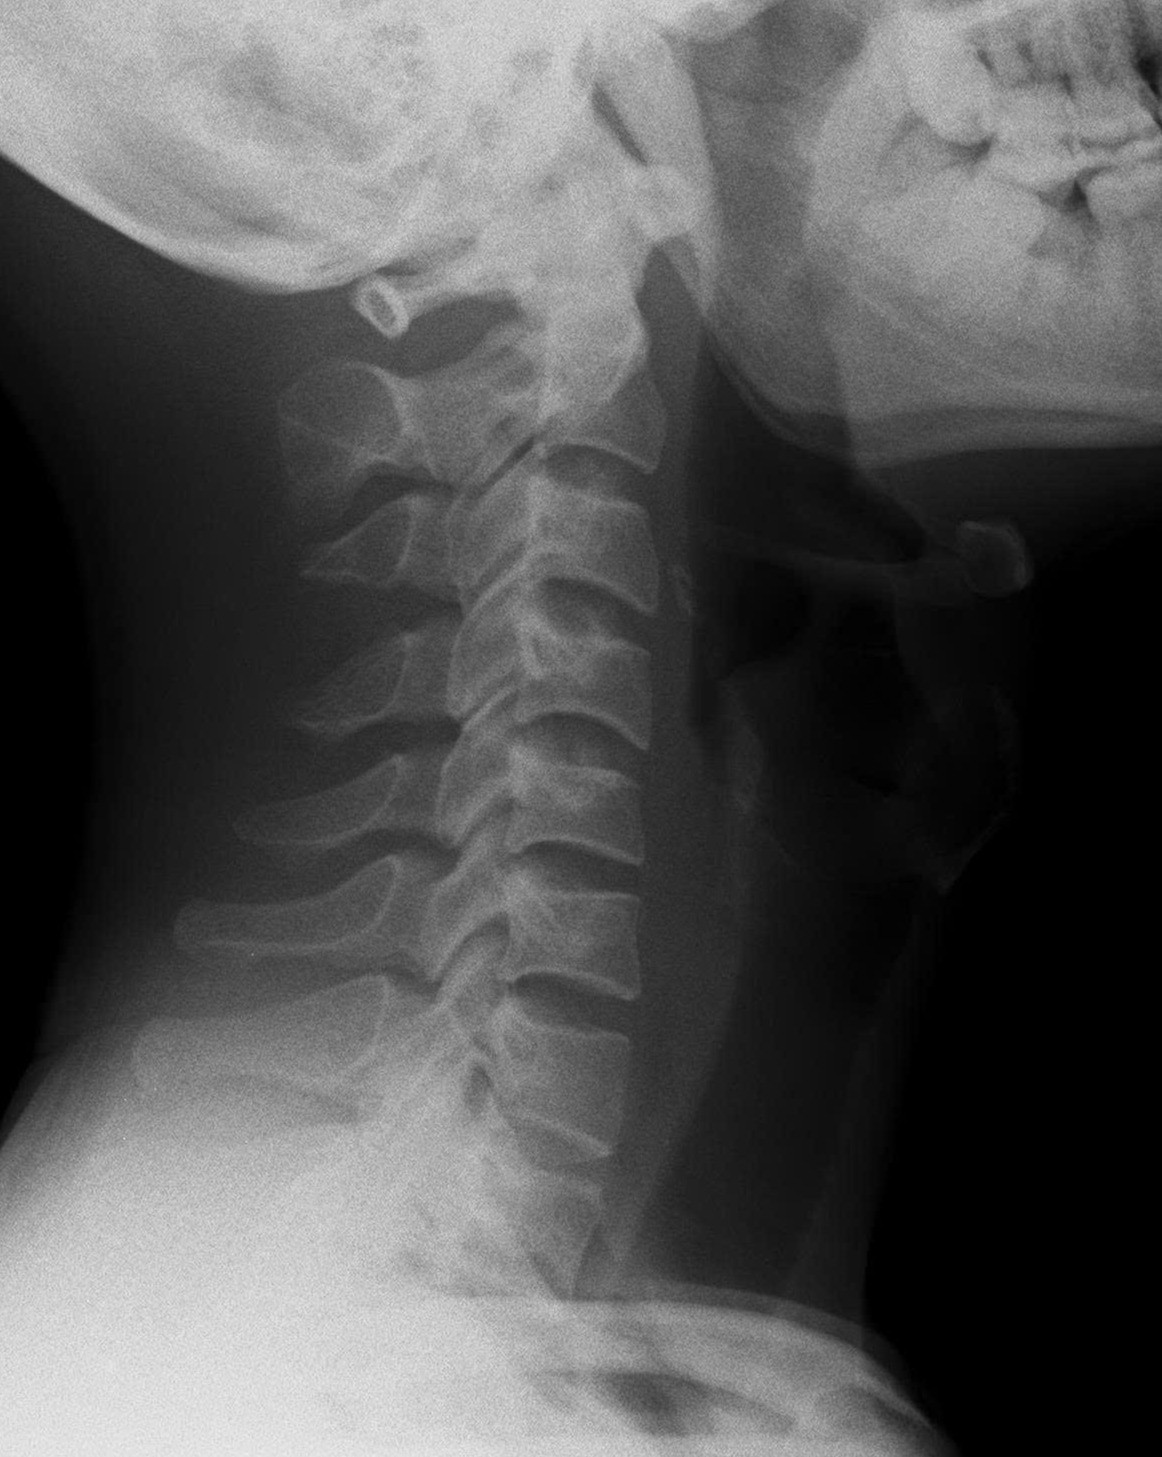

Kết quả chụp X-quang cho thấy cột sống cổ của bệnh nhân mất độ cong sinh lý, khiến các đốt sống cổ gần như xếp dọc thay vì có độ ưỡn ra trước như bình thường.

Tiến sĩ, bác sĩ Ngô Thị Kim Oanh - Phó Trưởng khoa Châm cứu - Dưỡng sinh, Bệnh viện Đại học Y Dược TPHCM - Cơ sở 3 cho biết, ở người trưởng thành khỏe mạnh, cột sống cổ có độ cong nhẹ về phía trước - gọi là độ ưỡn sinh lý giúp phân bổ đều lực từ đầu xuống vai và thân trên, hấp thu lực chấn động từ các hoạt động thường ngày (đi, đứng, chạy...), giảm tải trọng lên đĩa đệm và khớp liên đốt sống

Khi đường cong này bị mất, cột sống trở nên “thẳng như cây gậy” - làm tăng áp lực lên các đĩa đệm, khớp, dây chằng và cơ quanh cổ. Về lâu dài, điều đó có thể dẫn đến thoái hóa sớm, thoát vị đĩa đệm cổ, chèn ép rễ thần kinh hoặc tủy sống, gây ra các triệu chứng như đau, tê tay, chóng mặt, thậm chí yếu cơ.